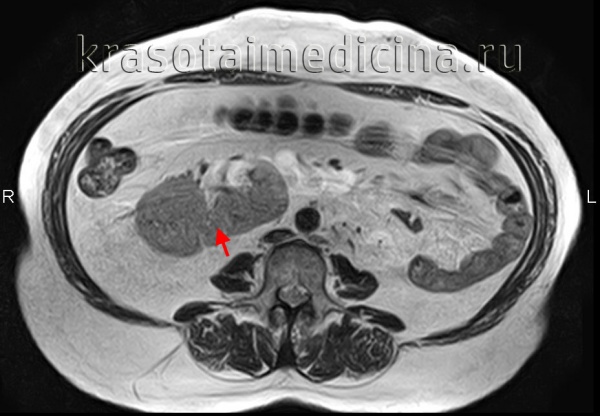

Лучевая диагностика подковообразной почки

• Врожденная аномалия развития, в которой почки сращены перешейком в области нижних полюсов

б) Визуализация:

• Лучший диагностический критерий:

о Две почки на противоположных сторонах тела со сращением нижних полюсов по средней линии

• Локализация:

о Эктопическая, расположены ниже, чем нормальные почки

о Перешеек обычно расположен кпереди от аорты и каудально по отношению к слиянию подвздошных вен